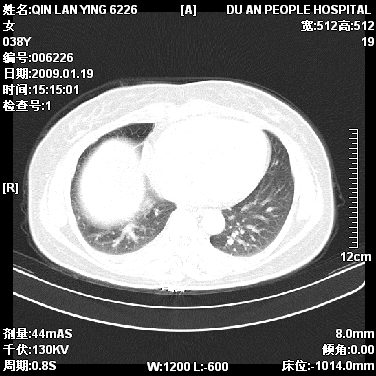

女,38岁,胸疼1个月。wbc:1万4

1)右肺中央型肺癌并右肺上叶阻塞性肺炎、节段性肺不张,纵隔淋巴结转移、右侧胸膜转移、肝脏转移。2)右侧胸腔少量积液。

1、右侧中央型肺癌并阻塞性肺不张,纵隔内、主动脉弓旁、右肺门淋巴结及肝脏转移可能性大,建议纤支镜进一步检查。

2、右侧胸腔积液。

本病例有几个容易诊断的地方:1、右肺上叶前段支气管闭塞,肺不张。2、淋巴结明显肿大。3、肝脏多个类圆形低密度影呈“牛眼征”改变,高度提示转移。

从影像学角度分析      右肺上叶中央型肺癌,并阻塞性不张、肺炎,纵隔淋巴结、膈顶淋巴结转移。

肝内两个大小不等低密度结节,内可见更低密度影,首先考虑肝内转移瘤,但联想到患者wbc1万4,建议楼主还是做个增强比较明确,除外肝脓肿的可能。